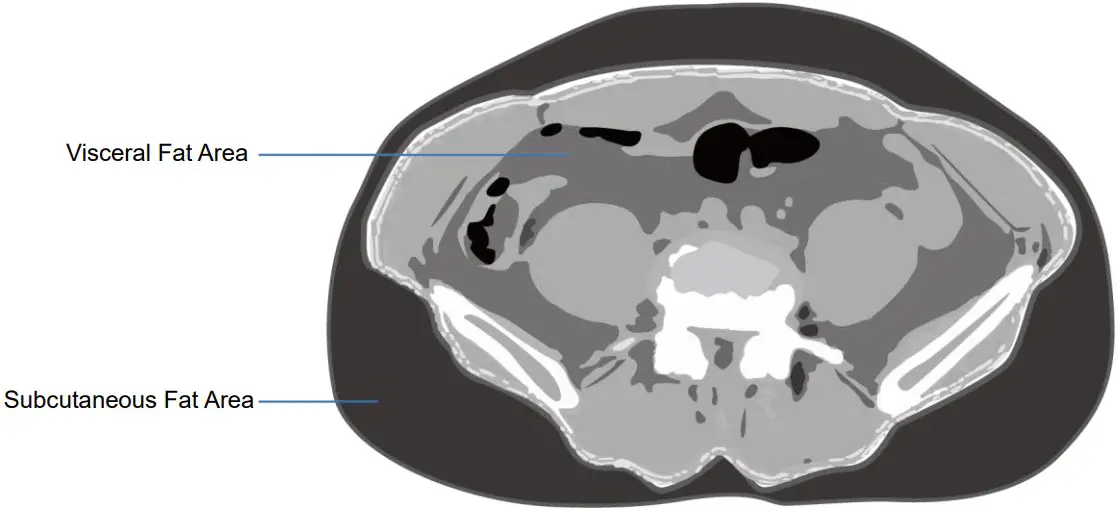

C. Visceral Fat Area

Visceral fat refers to fat accumulated around the intraperitoneal mesentery and the periphery (a broad membrane striking the abdominal wall from the lower part of the stomach). Visceral fat area is the cross sectional area of the fat in between the 4th and 5th lumbar vertebrae. As visceral fat accumulates, insulin is excessively secreted and cardiovascular diseases tends to increase. Thus, it is imperative to be cautious with the accumulation of visceral fat.

Moreover, even if the body fat percentage of the body weight falls within the standard range, one should aim for a healthy diet if there is an excessive visceral fat accumulation (refraining from eating sugar rich food, fatty food, refined grains, etc.) It is also important to participate in cardiovascular exercise in preventing accumulation of excessive visceral fat.

| Visceral Fat Area (0.0 ~ 100.0cm²) | 79.8 |

D. Subcutaneous Fat Area

The subcutaneous fat area is located between the dermis and fascia of the skin and represents fat that serves to store nutrients, block heat, absorb shock, etc. The subcutaneous fat area is measured by measuring the cross section between 4th and 5th lumbar vertebrae to the outside of the peritoneum. The subcutaneous fat has less association with diseases in comparison to the visceral fat but should be watched with caution as excessive accumulation may cause increase in weight, causing musculoskeletal disorders.

| Subcutaneous Fat Area (0.0 ~ 200.0cm²) | 128.7 |

E. Visceral to Subcutaneous Fat Ratio (VSR)

Visceral to Subcutaneous Fat Ratio (VSR) refers to the value of the visceral fat area divided by subcutaneous fat ratio.

Visceral to Subcutaneous Fat Ratio(VSR) = Visceral Fat Area / Subcutaneous fat Ratio

| VSR (0.0 ~ 0.4) | 0.62 |

Even if the fat percentage is identical, the degree of risk to health varies depending on the location of fat distribution. When fat accumulates in the abdomen and abdominal obesity occurs, it is vulnerable to type 2 diabetes, hyperlipidemia, high blood pressure, coronary artery disease. In particular, as the amount of visceral fat accumulates, there is a higher risk of getting the disease mentioned above. Visceral to Subcutaneous Fat Ratio (VSR) is one of the criteria in assessing the accumulation of visceral fat, with individuals with values of over 0.4 considered obese when it comes to intra-abdominal obesity.

Visceral fat is highly influenced by one’s lifestyle and habits, and thus controlled diet and exercise alone can bring a lot of changes. Exercise therapy particularly plays a major role in the reduction of visceral fat, so if one’s VSR is over 0.4, daily cardiovascular exercise of at least an hour is recommended.